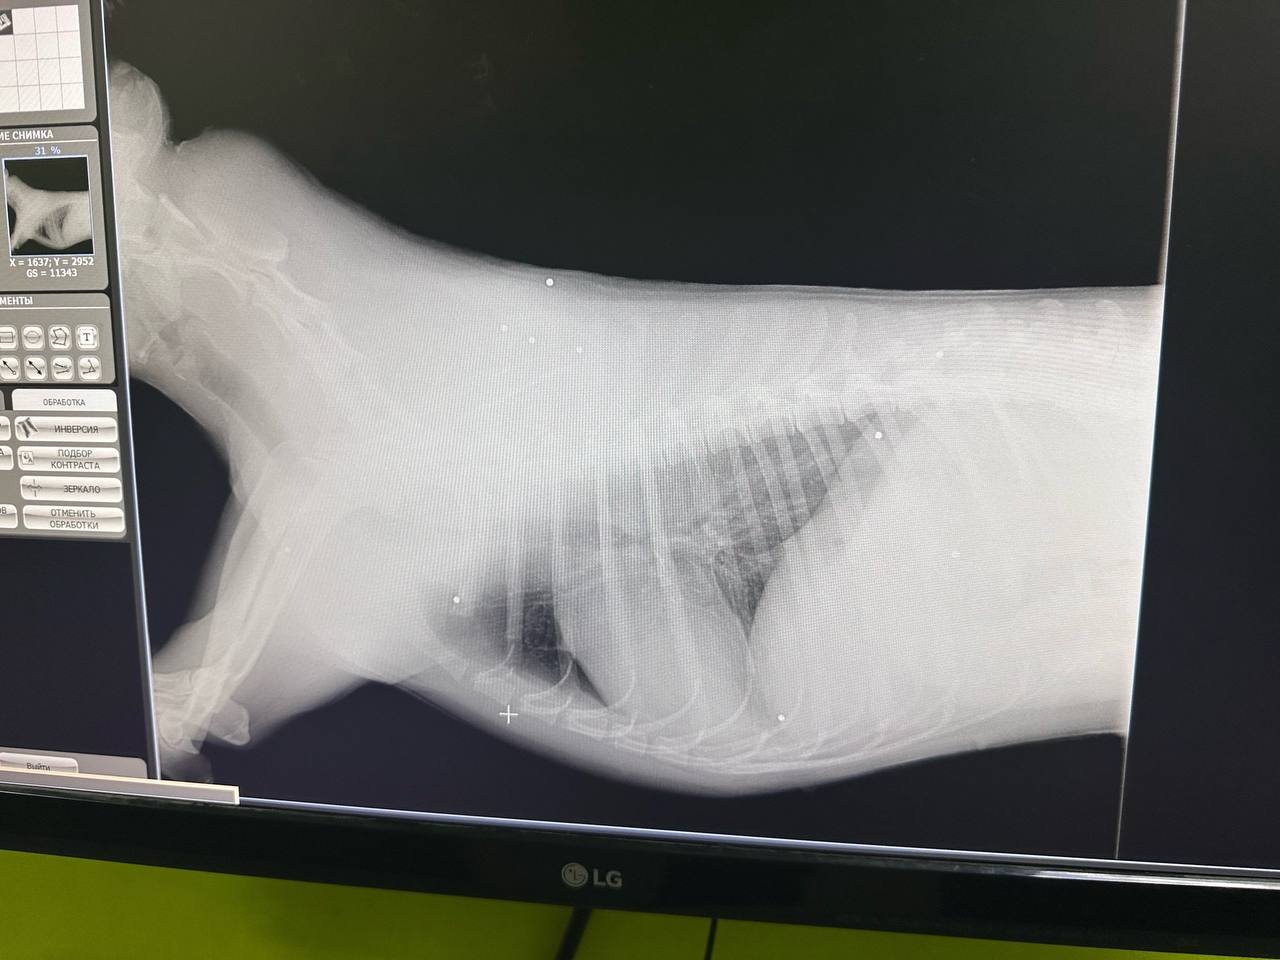

На место выехали волонтёры. Из одного мешка чёрная собака смогла убежать, во втором находилась светлая собака с окровавленной головой, которая не могла подняться. Животное срочно доставили в ветеринарную клинику. Врачи установили, что собаке выстрелили в голову - дробь разошлась по спине и телу.

Пострадавшая собака, получившая кличку Умка, находится в тяжёлом состоянии в стационаре. У неё отсутствует чувствительность задних лап, состояние позвоночника уточняется. По бирке выяснилось, что ранее животное было отловлено, стерилизовано и вакцинировано, после чего возвращено в прежнюю среду обитания.